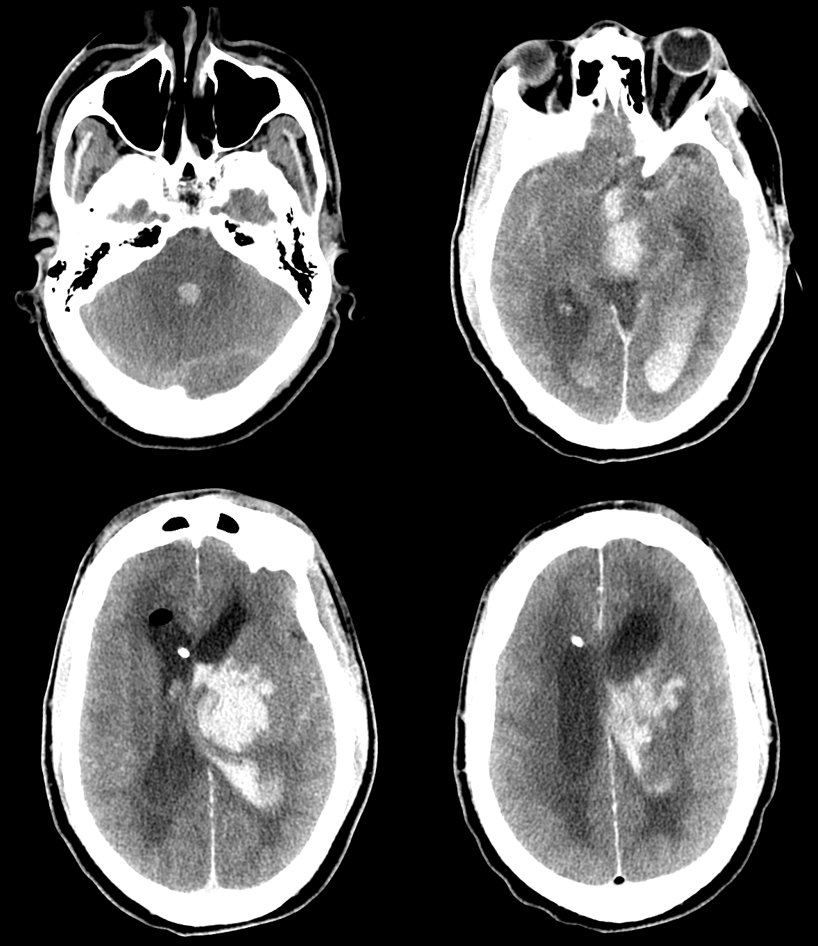

One more! Presented with basal ganglia hemorrhage

Things look much worse by the time patient is transferred to our place

Here they are…